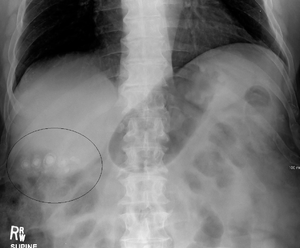

Free intra-abdominal air below the diaphragm. Body-packing with multiple foreign bodies ("balls" of hashish).

Body-packing with multiple foreign bodies ("balls" of hashish).